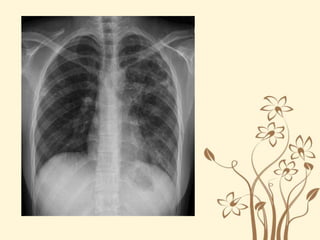

THỰC HÀNH ĐỌC XQUANG